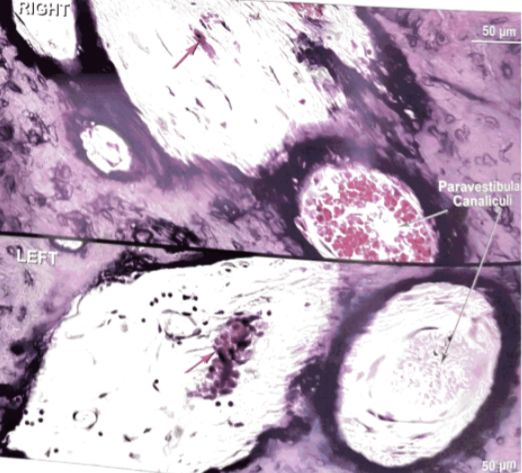

09 前庭旁小管静脉

Ikeda和Sando研究了27例MD患者的颞骨中前庭旁小管(Vein in paravestibular canaliculus ,PVC)及其内容(静脉)发现,在4例(15%)MD患者中,PVC的一部分没有静脉,而对照组样本中从未观察到。PVC中的静脉是从内耳排出的两个主要静脉之一。它从前庭开始,一直延伸到后颅窝,目前已经证明,这种静脉的重要性在于它是前庭系统的排水通道,并且与ES的结蹄组织静脉丛(之后流向乙状窦和岩下窦或颈静脉球)有联系。因此,该静脉可能在内耳的流体动力学中起作用。可以认为PVC静脉的异常可能是MD患者内淋巴水肿病理生理学的一个因素。